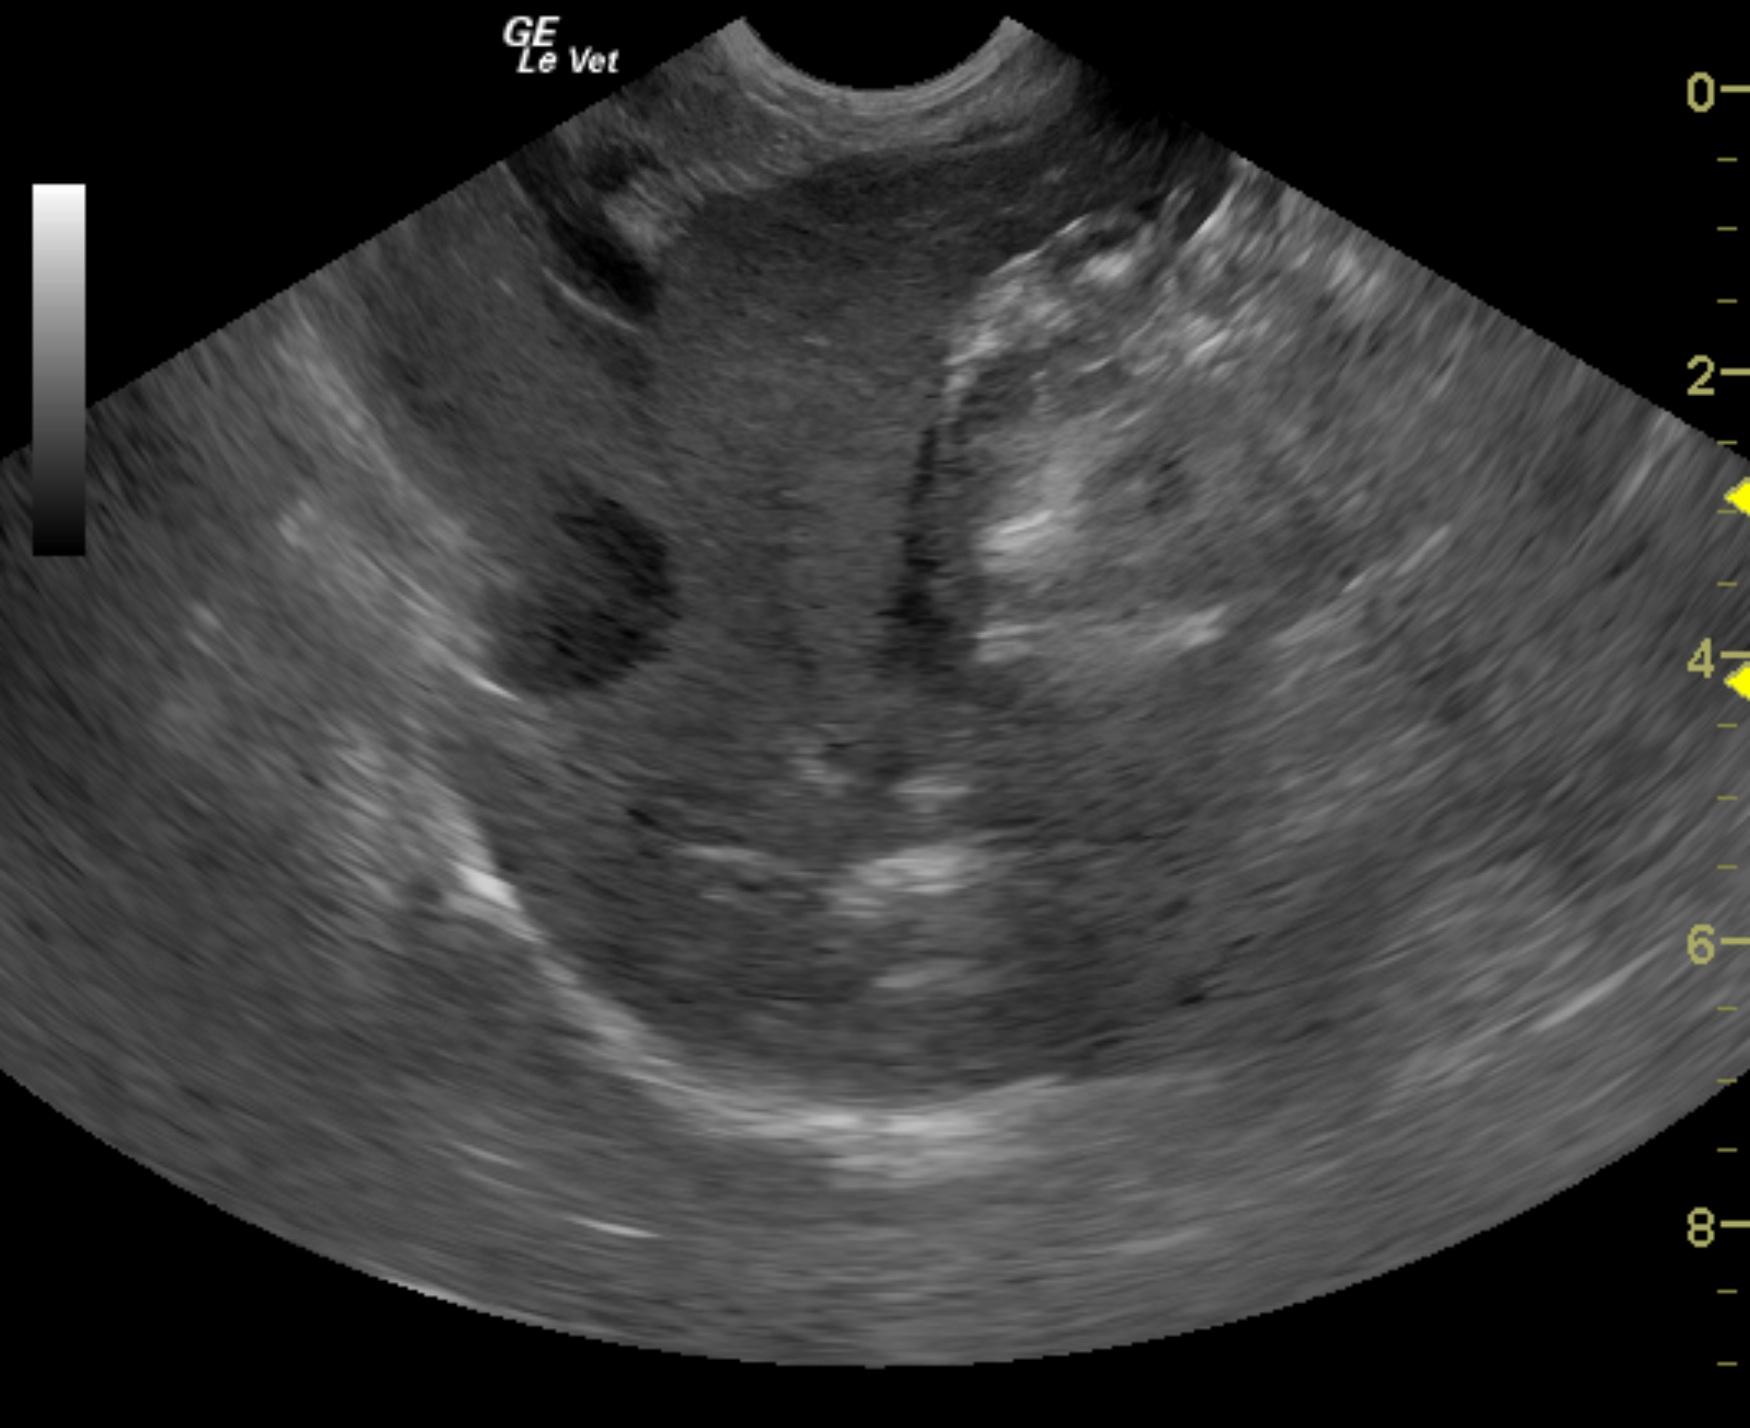

This 8 year old MN Jack Russull Terrier dog initially presented with abdominal distension and ascites. Chemistry revealed low total protein at 4.2, low albumin at 1.9, phosphorus low at 1.0, calcium low at 8.1, cholesterol was high at 332. Urine protein to creatinine ratio was high at 5.4, microalbuminuria was high at >30. Urinalysis reveled protein of 3+, blood 1+ and transitional epithelia elevated at 2-3.

This 8 year old MN Jack Russull Terrier dog initially presented with abdominal distension and ascites. Chemistry revealed low total protein at 4.2, low albumin at 1.9, phosphorus low at 1.0, calcium low at 8.1, cholesterol was high at 332. Urine protein to creatinine ratio was high at 5.4, microalbuminuria was high at >30. Urinalysis reveled protein of 3+, blood 1+ and transitional epithelia elevated at 2-3.